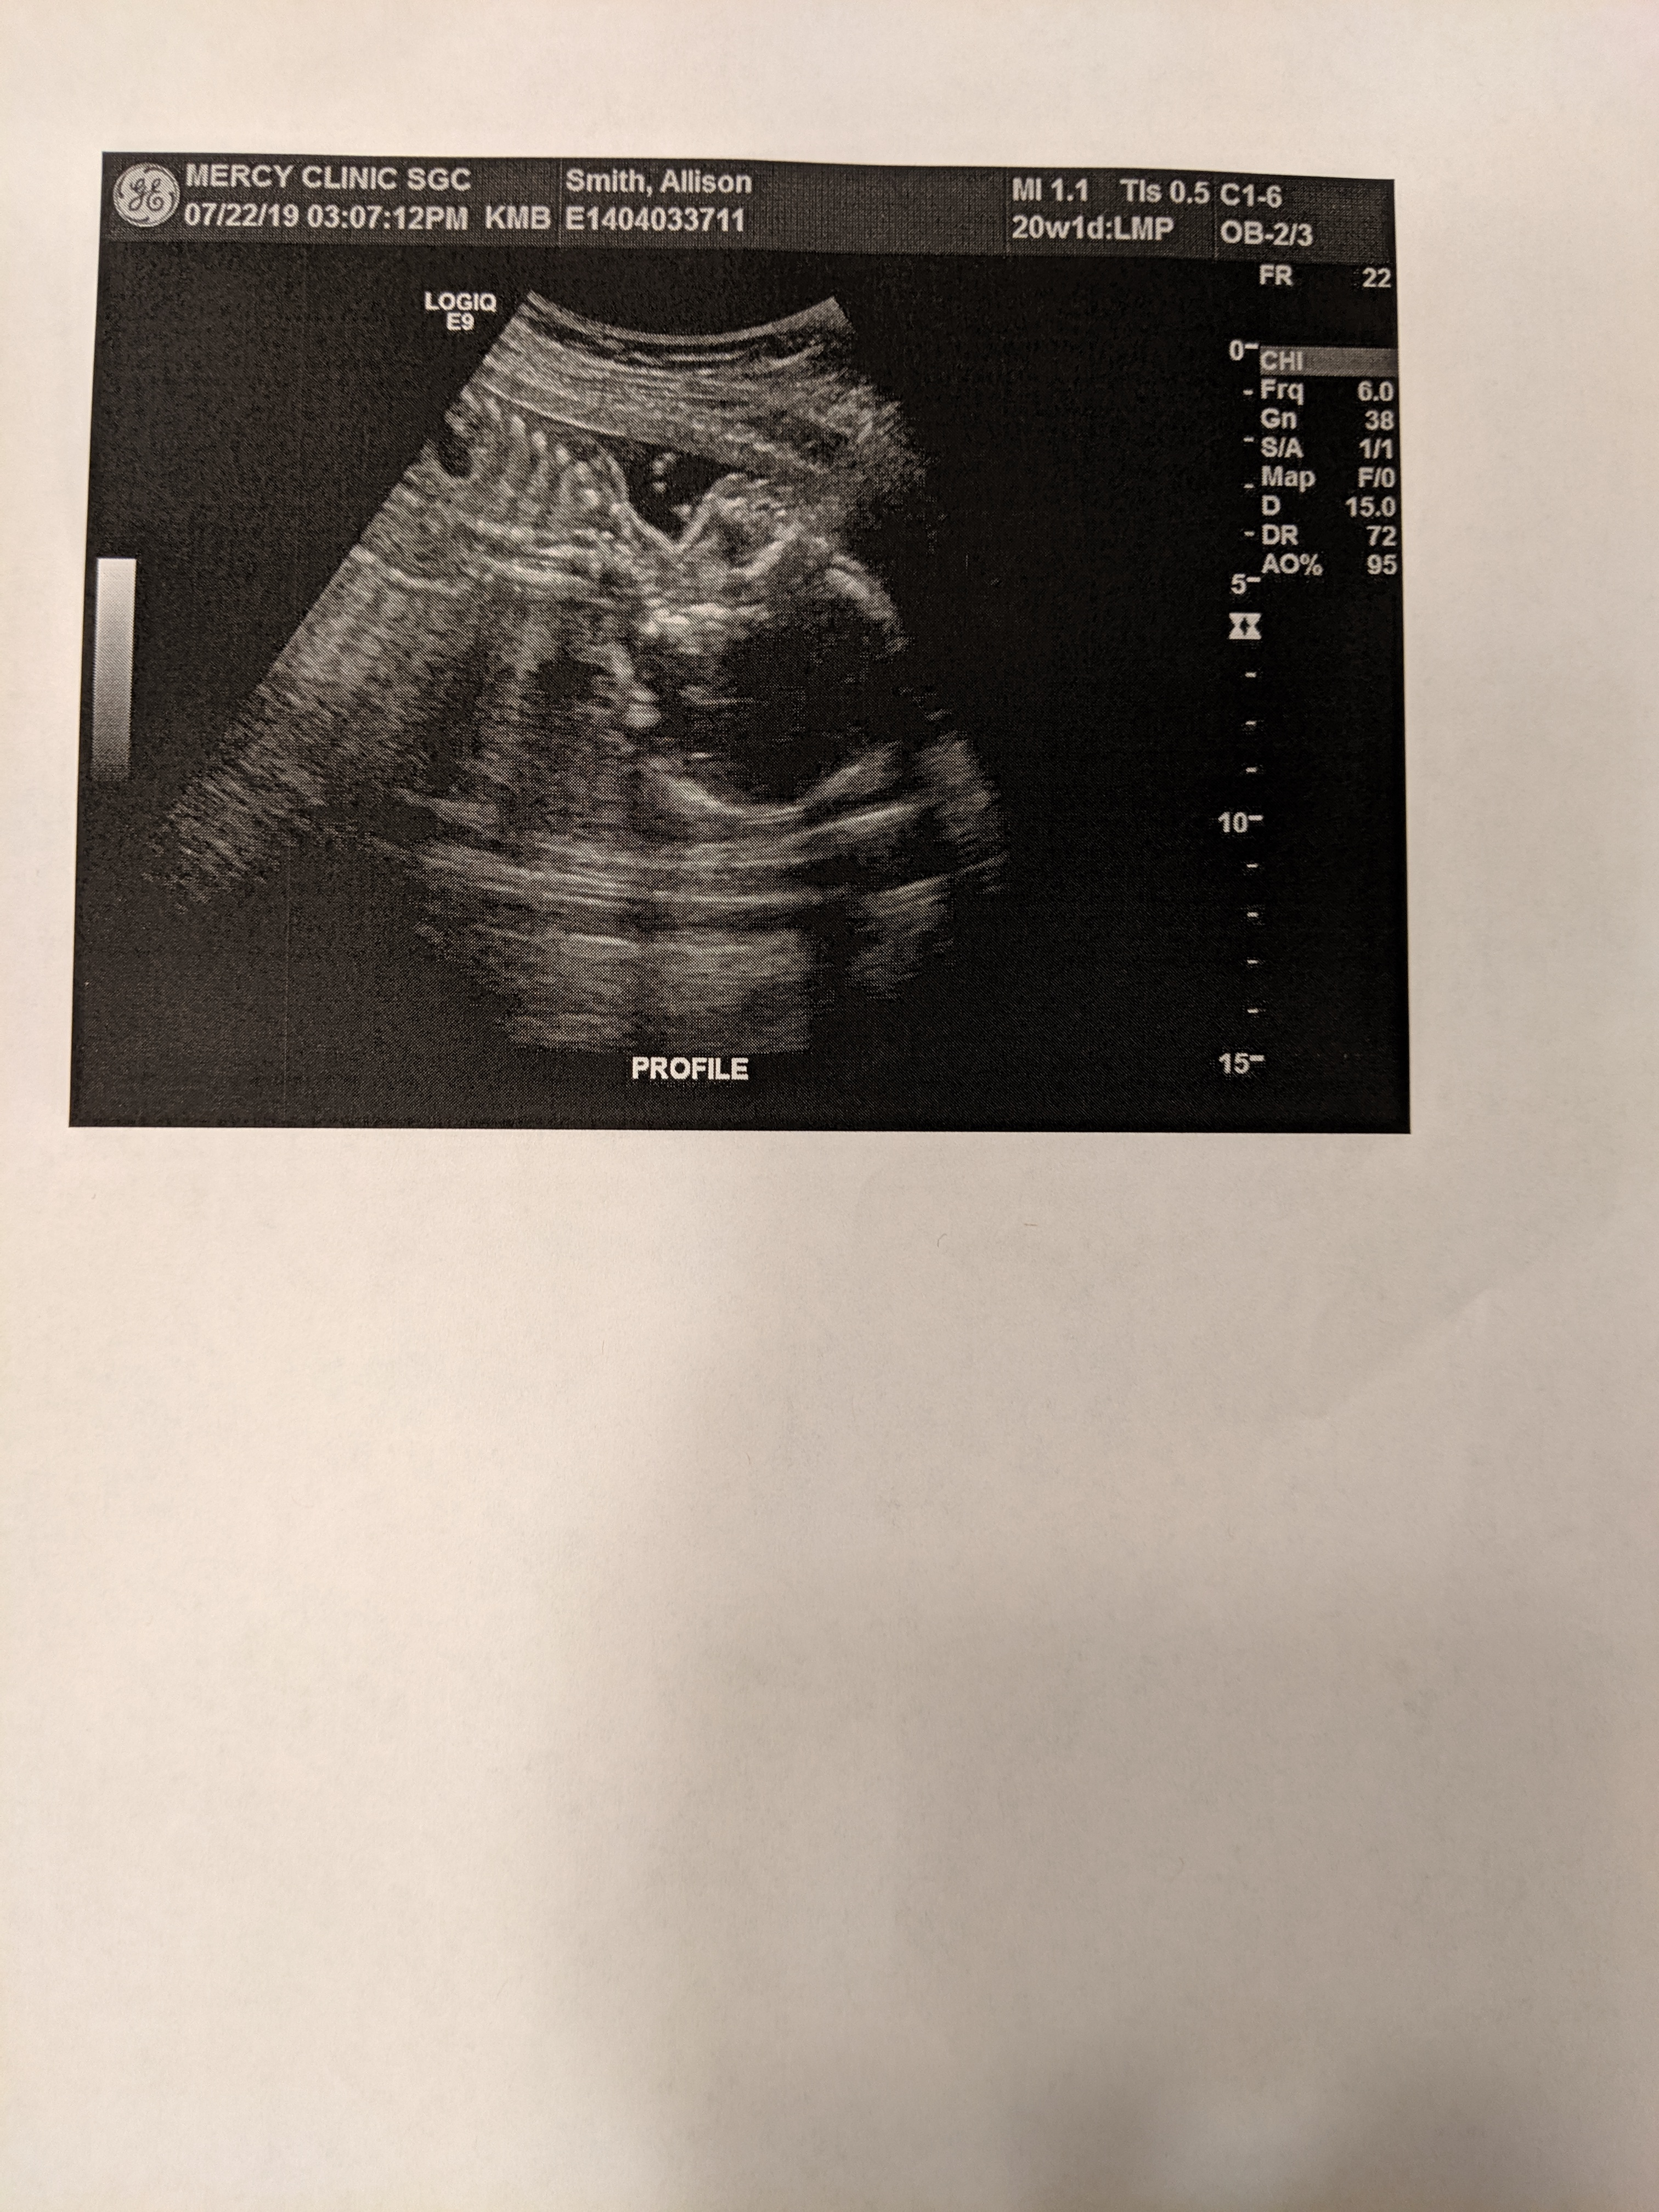

Exactly 20 weeks today. Wish we could post video here because you should’ve seen it squirm...took 90 minutes to get clear views because it flipped every 30 seconds...everything is looking good and we had no unwanted gender reveals!